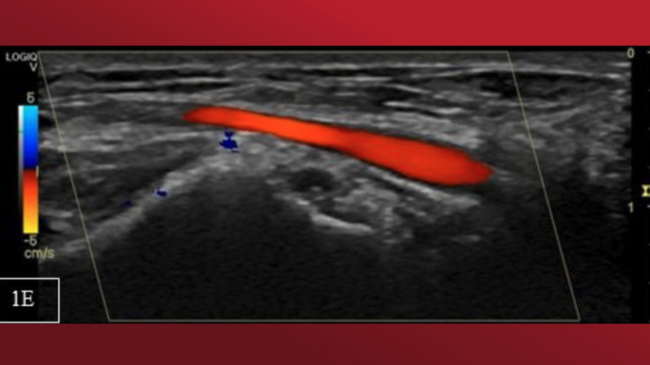

A 63-year-old man with a history of smoking, panic attacks, and positive treadmill test was referred for invasive coronary angiography (CA). By a right radial artery (RA) approach, there was difficulty advancing the sheath and the standard guidewire. The patient complained of intense pain, anxiety, and discomfort. Fluoroscopy depicted severe RA spasm (RAS) (Figure 1A and Video Series). Prolonged occlusion flow-mediated dilation and balloon-assisted techniques failed. Sheath withdrawal avulsed an RA fragment (2 cm long) protruding through the access site (Figure 1B).

In our patient, repeated administration of local anesthesia with subcutaneous lidocaine and mild sedation with 1 mL of midazolam minimized nervousness, distress, and soreness perception, while serial delivery of subcutaneous and intra-arterial verapamil and nitroglycerin provoked local RA vasodilation tackling the spasm. The RA was then punctured proximally (Figure 1C). The avulsed RA fragment was excised (Figure 1D)and minimal bleeding required no further intervention. Radial pulse remained palpable, possibly because the adventitia remained intact or the avulsed RA fragment formed a minor RA branch. Histopathology was unavailable. CA was unremarkable (Video Series) and at 1-month follow-up, vascular ultrasound portrayed uncompromised blood flow (Figure 1E).